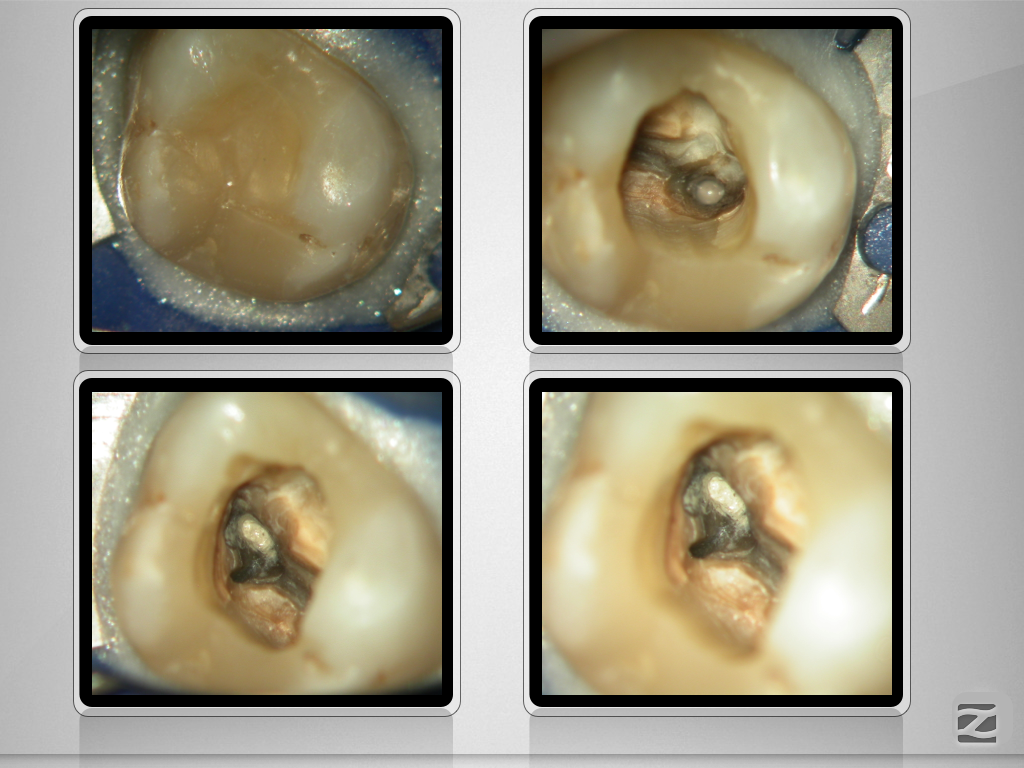

27D.002

Konfluierende Kanäle